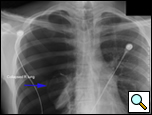

Patients who have had a second episode of spontaneous pneumothorax are those most likely to be considered for thoracoscopic pleurectomy and apical blebectomy. However, patients with a first episode of spontaneous pneumothorax who have a prolonged air leak (greater than 72 hours), incomplete expansion of the lung (Figure 1), bilateral pneumothoraces, associated hemothorax, tension pneumothorax (Figure 2), or a bleb on their CT scan (Figure 3) should be offered surgery at the time of the first occurrence [1]. Patients who have had a spontaneous pneumothorax and whose occupation places them at risk for a second episode or places them in a situation where medical intervention is not readily accessible should be considered for surgery. Therefore divers, pilots, submarine personnel, and those that work or live in the wilderness or space are suitable patients [1].

| Figure 1: Chest x-ray showing incomplete expansion of lung after chest tube placement. | Figure 2: Chest x-ray showing tension pneumothorax with mediastinal shift. | Figure 3: CT Scan showing apical bleb. |